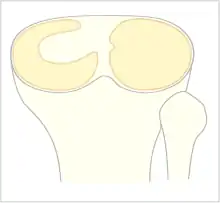

The Watanabe classification of discoid lateral meniscus is: (A) Incomplete, (B) Complete, and C) Wrisberg-ligament variant [2] Normally, the meniscus is a thin crescent-shaped piece of cartilage that lies between the weight bearing joint surfaces of the femur and the tibia. It is attached to the lining of the knee joint along its periphery and serves to absorb about a third of the impact load that the joint cartilage surface sees and also provides some degree of stabilization for the knee. There are two menisci in the knee joint, with one on the outside (away from midline) being the lateral meniscus and the inner one (towards midline) the medial meniscus. A discoid meniscus is a congenital anomaly of the knee found in 3% of the population (up to 15% in Asia). It typically affects the lateral meniscus and may be found bilaterally (20%). Instead of the narrow crescent shape, as seen in a normal meniscus above, a discoid meniscus is thickened, and has a fuller crescent shape. In addition, a discoid meniscus does not taper as much towards the center of the joint and is shaped like a disc. The thickness of the meniscus, its diminished vascular blood supply, and in some instances, weak capsular attachment, makes it more prone to tears compared to a normal meniscus. The anomaly in itself is asymptomatic; however, a tear of the meniscus can result in pain, swelling, and snapping in the affected knee. The orthopedic classification of discoid menisci includes: complete, incomplete or Wrisberg-ligament types as depicted here. Coverage of the lateral tibial plateau determines the designation of complete or incomplete. The Wrisberg-ligament type has an abnormal posterior attachment by attaching to part of the posterior cruciate ligament.